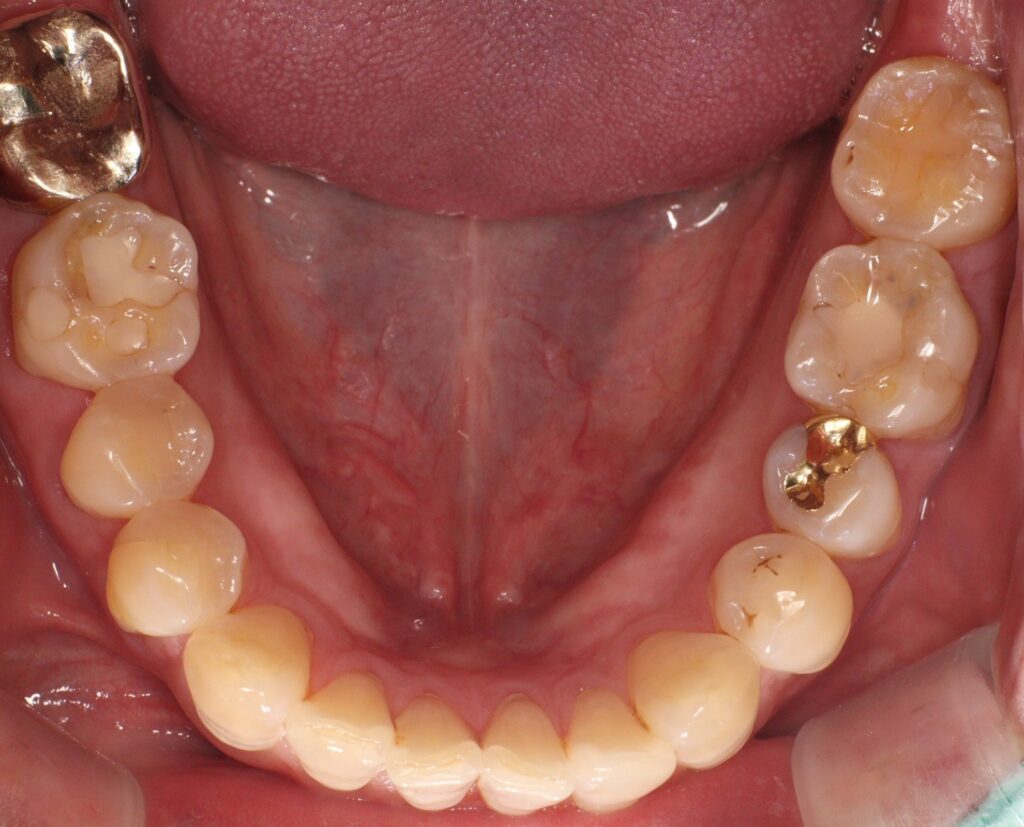

이번 증례에서는 구치부 치아의 손상으로 인해

레진 빌드업을 시행한 과정을 살펴보며,

치료 전 상태와 빌드업 과정,

그리고 회복된 결과를 중심으로

자세히 안내드리고자 합니다.

환자분께서는 아래쪽 어금니에 떼운 재료가

오래 되어 광화문치과에 내원해 주셨는데요.